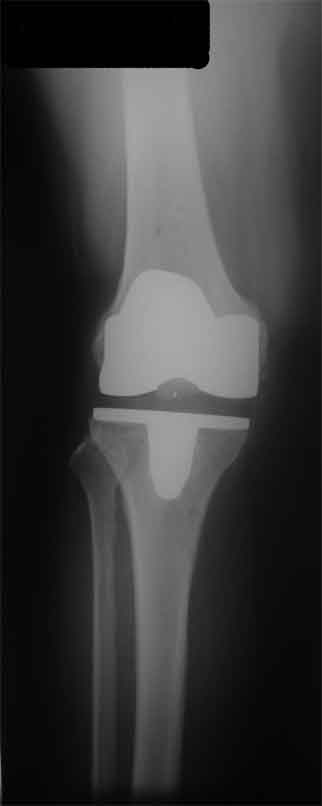

Стрессовый снимок

Оперирована пациентка 42 лет, избыточного веса. Выполнено б/ц протезированние коленного сустава эндопротезом LCS. Послеоперационный период гладкий, в срок 2 мес. после операции объем движений удовлетворительный, сгибание до острого угла, разгибание полное. В 3,5 мес. во время падения подвернула ногу, после чего появилась. клиника медиолатеральной нестабильности. В течении 3 недель фиксация в туторе. При повторном осмотре жалобы на дискомфорт в коленном суставе, «щелканье», неустойчивость в суставе. Вопросы/варианты дальнейшей тактики лечения пациентки.